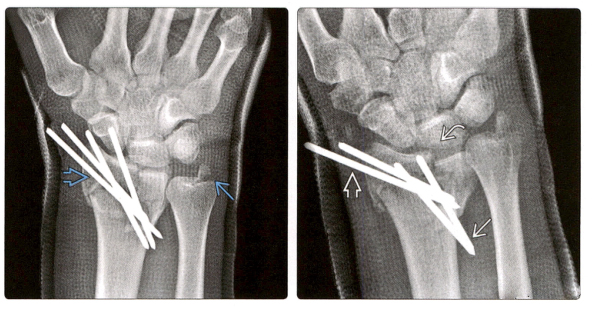

4. На переднезадней рентгенограмме видна дорсальная пластина, используемая для стабилизации фрагмента полулунной ямки при сильно оскольчатом переломе дистального отдела лучевой кости. Перелом дистального отдела локтевой кости был деформирован, а после заживления перелома ДРЮС значительно деформировался и увеличился.

5. (Фото слева) Боковая рентгенограмма после установки ладонной пластины при переломе дистального отдела лучевой кости показывает, что 2 дистальных винта доходят до лучезапястного сустава. Нормальный наклон ладоней до сих пор не восстановлен.

(Справа) Перелом зажил через 6 месяцев, но неправильно расположенный винт задел и изменил форму проксимального отдела ладьевидной кости, возможно, повредив ладьевидно-полулунную связку. Полулунная кость также может быть поражена и повреждена.